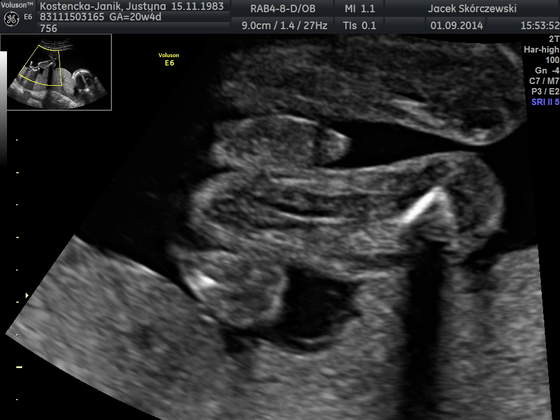

ja już po połówkowym i wszystko ok.

i nie ma wątpliwości będzie Maksiu:

IMG_20140901_1_1.jpg

u prywatnego młody ważył 358 g, a dzień później na nfz 419g